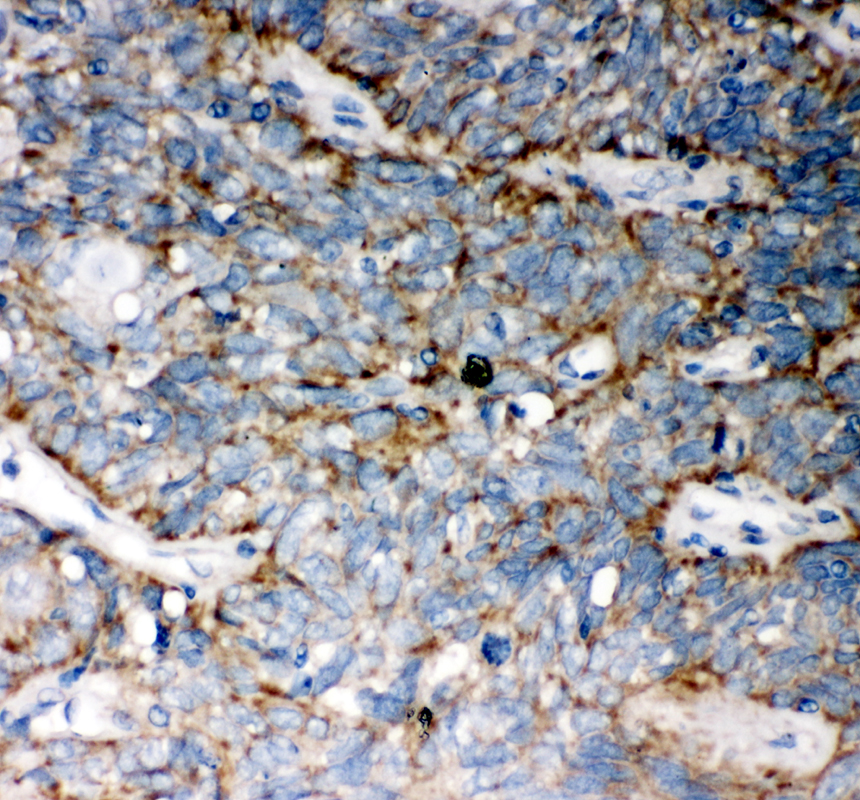

IHC analysis of WNT5A using anti-WNT5A antibody (BA2839) .

WNT5A was detected in a paraffin-embedded section of human lung cancer tissue. The tissue section was incubated with rabbit anti-WNT5A Antibody (BA2839) at a dilution of 1:200 and developed using HRP Conjugated Rabbit IgG Super Vision Assay Kit (Catalog # SV0002) with DAB (Catalog # AR1027) as the chromogen.